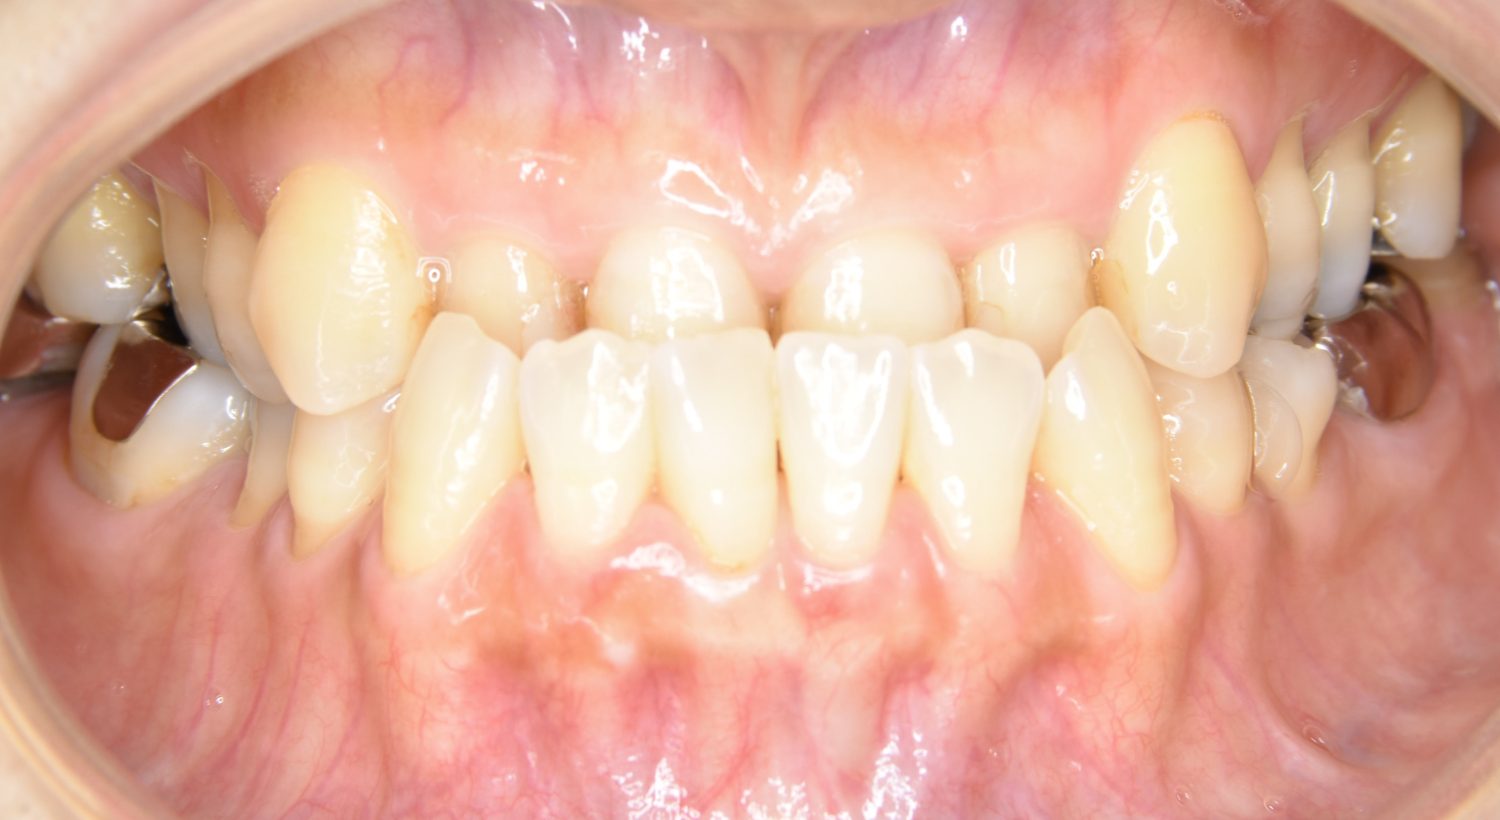

叢生の症例紹介①

Before

主訴

前歯のガタガタが気になる。

治療内容

上顎左側第一小臼歯を抜歯し、アライナー(インビザライン)にて治療を行いました。

治療費

1,150,000 円(税込)

治療期間

23ヶ月

通院回数

13回

想定されたリスク

※歯根吸収、歯肉退縮、歯髄壊死、顎関節症状

※アライナー(インビザライン)は日本の薬機法未承認の矯正装置であり、医薬品副作用被害救済制度の対象外となる場合があります。

左上の側切歯が完全に内側に入り込んでいる状態でした。左上の第一小臼歯のみ抜歯を行い治療を行うことで機能面および審美面を改善しました。